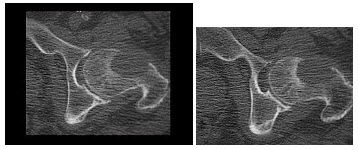

35、单项选择题

男,24岁,左侧髋部肿胀隐痛1月余,结合影像学检查,最可能的诊断是()

A.骨肉瘤

B.动脉瘤样骨囊肿

C.骨结核

D.骨转移瘤

E.骨脓肿